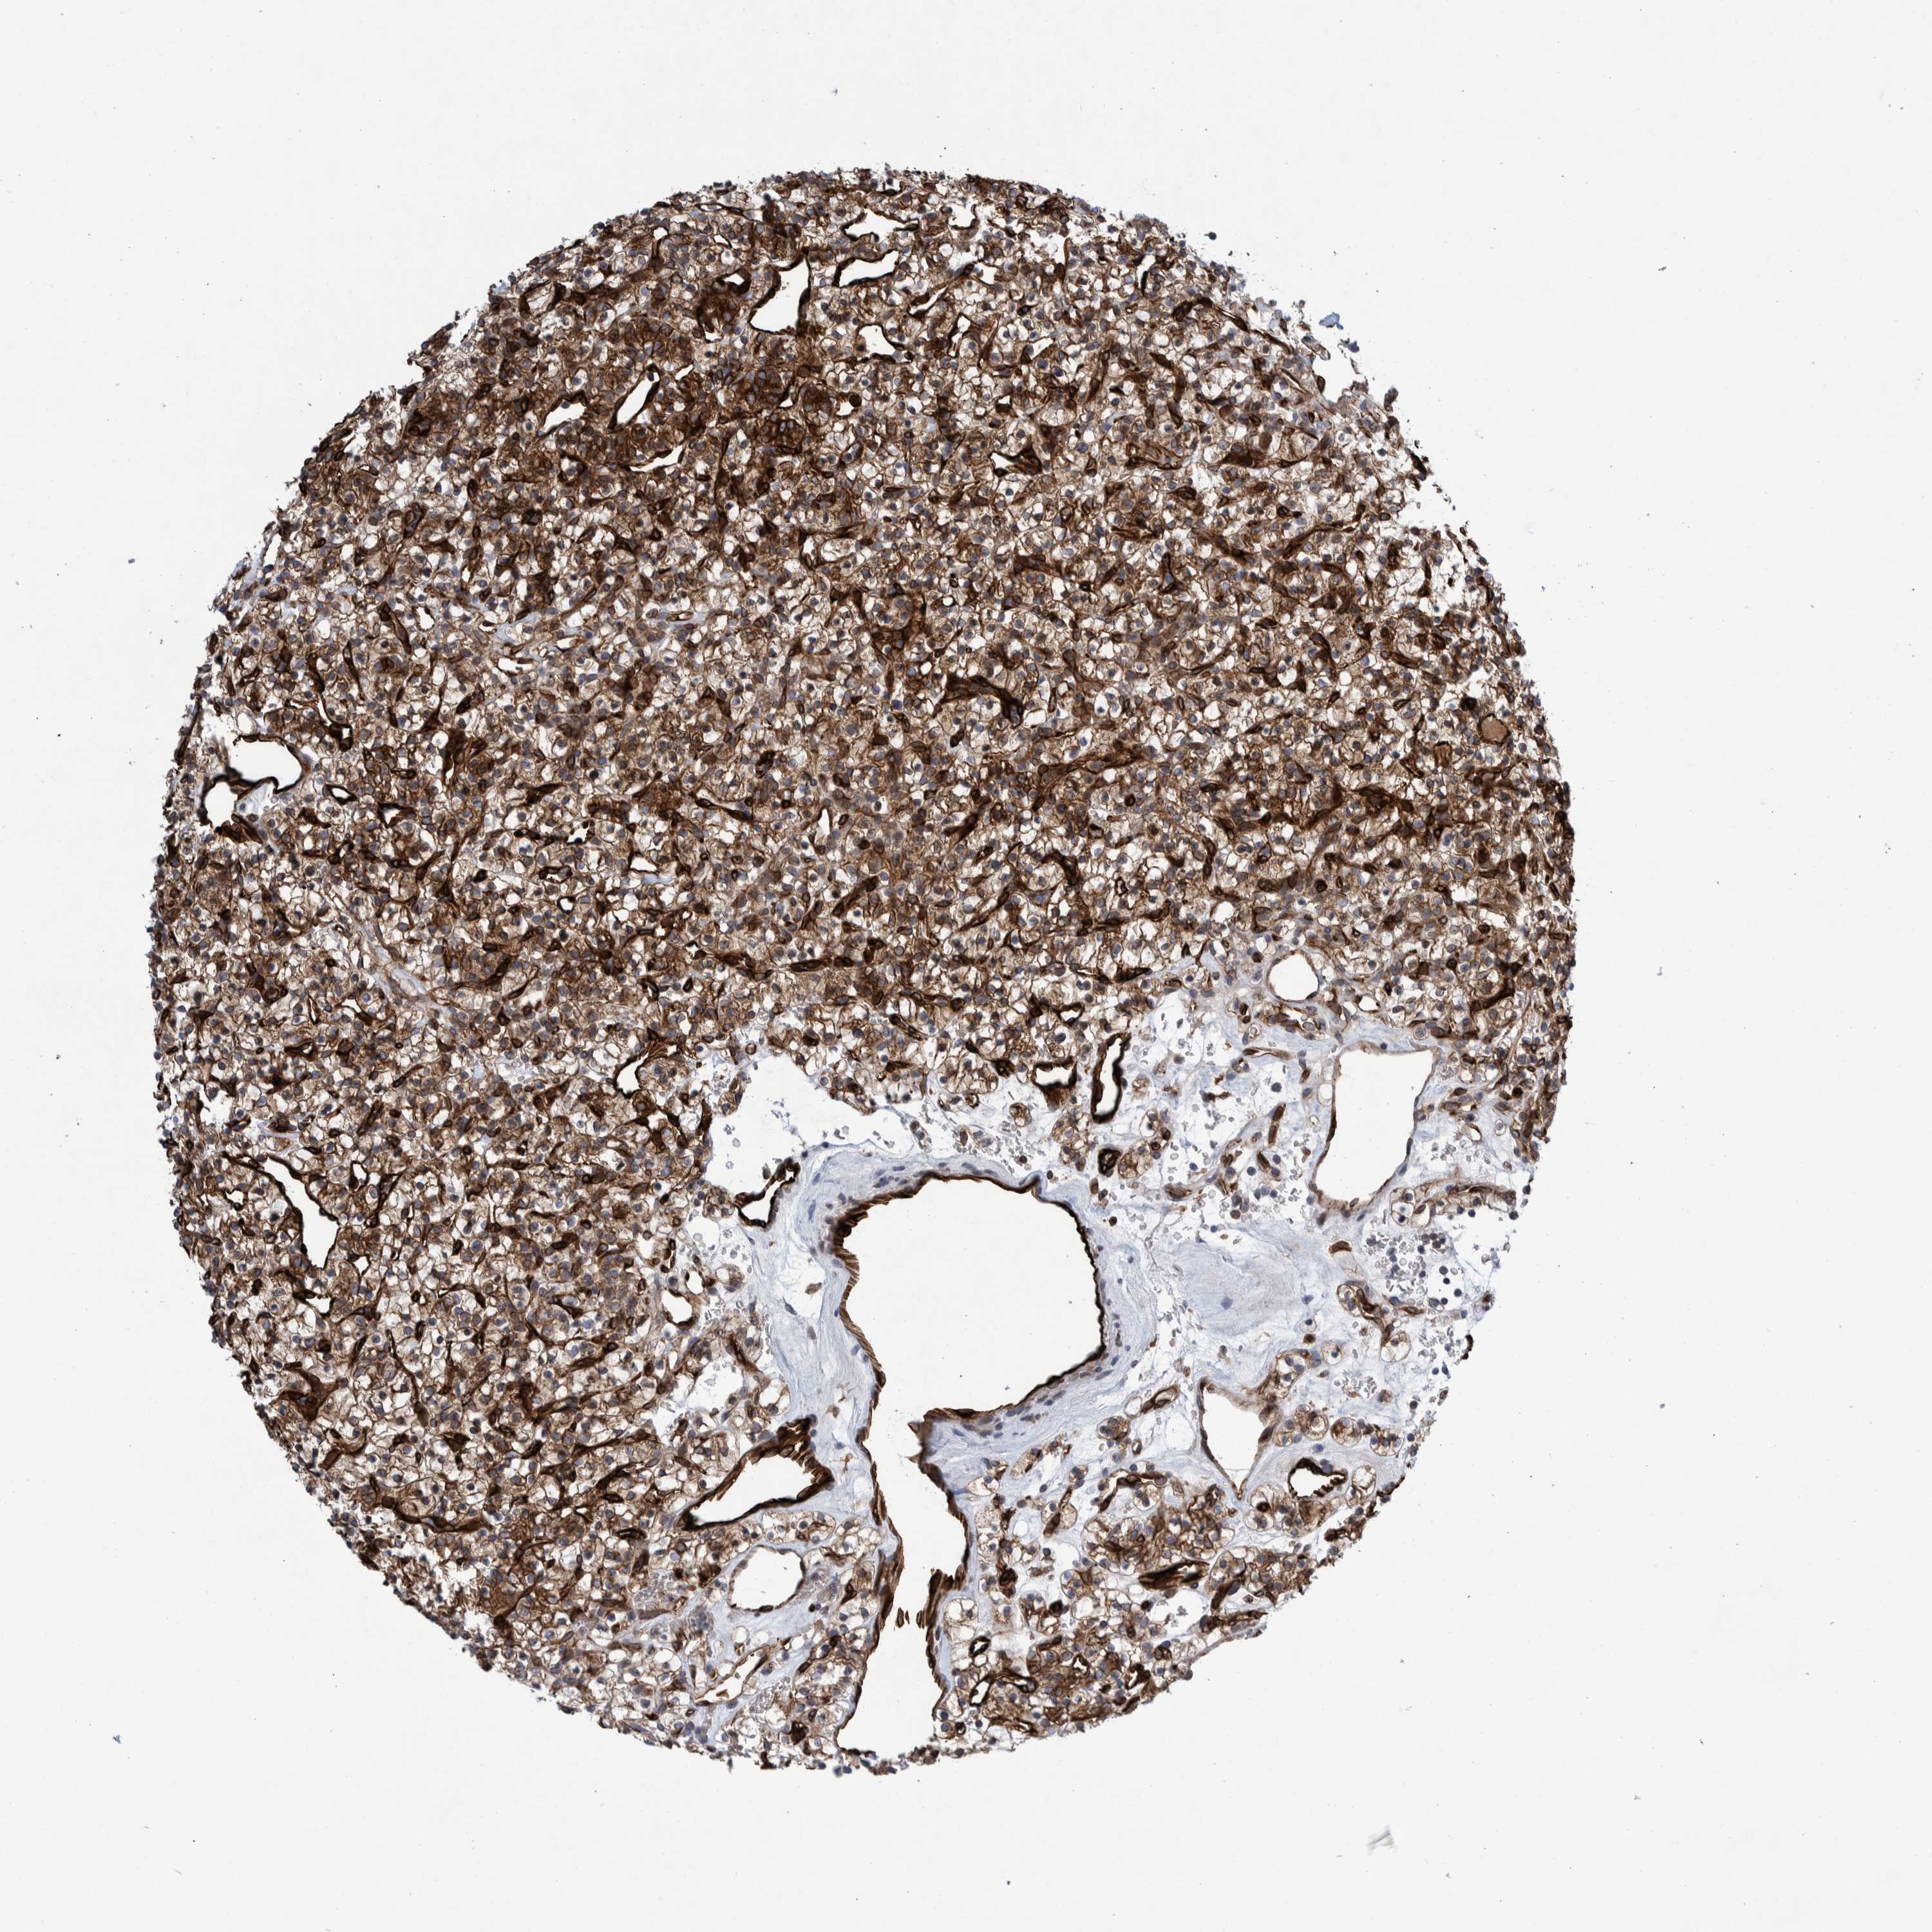

KIDNEY CHROMOPHOBE (TCGA) - Interactive survival scatter ploti

The Survival Scatter plot shows the clinical status (i.e. dead or alive) for all individuals in the patient cohort, based on the same data that underlies the corresponding Kaplan-Meier plots. Patients that are alive at last time for follow-up are shown in blue and patients who have died during the study are shown in red.

The x-axis shows the expression levels (FPKM) of the investigated gene in the tumor tissue at the time of diagnosis. The y-axis shows the follow-up time after diagnosis (years). Both axes are complimented with kernel density curves demonstrating the data density over the axes. The top density plot shows the expression levels (FPKM) distribution among dead (red) and alive patients (blue). The right density plot shows the data density of the survived years of dead patients with high and low expression levels respectively, stratified using the cutoff indicated by the vertical dashed line through the Survival Scatter plot. This cutoff is automatically defined based on the FPKM cutoff that minimizes the p-score. The cutoff can be changed by dragging the vertical line or by entering a cutoff value in the square labeled "Current cut-off".

Under the Survival Scatter plot the p-score landscape (black curve; left axis) is shown together with dead median separation (red curve; right axis). Dead median separation is the difference in median mRNA expression between patients who have died with high and low expression, respectively. It is calculated as follows: median FPKM expression of dead patients with high expression - median FPKM expression of dead patients with low expression. This is intended to aid the user in visually exploring custom cutoffs and the associated p-scores and dead median separation.

Individual patient data is displayed and can be filtered by clicking on one or more of the category buttons on the top of the page. Categories describing expression level and patient information include: high, low, alive, dead, female, male and tumor stages. The scale of the x-axis can be toggled between linear and log-scale by clicking on the "x log" button. Mouse-over function shows TCGA ID, patient information and mRNA expression (FPKM) for each patient.

& Survival analysisi

Kaplan-Meier plots summarize results from analysis of correlation between mRNA expression level and patient survival. Patients were divided based on level of expression into one of the two groups "low" (under cut off) or "high" (over cut off). X-axis shows time for survival (years) and y-axis shows the probability of survival, where 1.0 corresponds to 100 percent.

THEM6 is not prognostic in Kidney Chromophobe (TCGA)

Best expression cut offi

Based on the FPKM value of each gene, patients were classified into two groups and association between prognosis (survival) and gene expression (FPKM) was examined. The best expression cut-off refers the FPKM value that yields maximal difference with regard to survival between the two groups at the lowest log-rank P-value. Best expression cut-off was selected based on survival analysis .

When clicking on this number, the vertical dashed line indicating cut-off, the interactive survival plot, and the Kaplan-Meier curve will be adjusted to show results based on the best expression cut-off.

: 56.72

TCGA RNA samplesi

RNA-seq data is reported as average FPKM (number Fragments Per Kilobase of exon per Million reads), generated by the The Cancer Genome Atlas (TCGA) .

Normal distribution across the dataset is visualized with box plots, shown as median and 25th and 75th percentiles. Points are displayed as outliers if they are above or below 1.5 times the interquartile range. FPKM values of the individual samples are presented next to the box plot.

Average pTPM 48.7

Number of samples 64